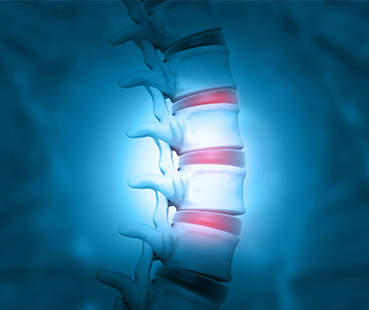

Orthopedists and orthopedic surgeons at NewYork-Presbyterian deliver exceptional care for patients with conditions of the bones and joints, helping them regain function and mobility. In 2025, our specialists evolved surgical techniques for better patient outcomes, fostered cross-specialty collaboration in pediatric spine surgery, leveraged artificial intelligence for improved diagnostics, focused on identifying health disparities in orthopedic cancers, and more. These advancements are providing comprehensive solutions that bring expert orthopedic care to the patients we serve and beyond.

Orthopedic specialists from Columbia are internationally renowned for their depth of experience and expertise in complex musculoskeletal disorders. They provide compassionate care for injuries in elite athletes; arthroplasty and minimally invasive procedures for individuals of all ages with joint disease; and surgery for complicated bone and joint disorders. With the goal to return function and mobility for patient, the team at Columbia remains on the cutting-edge of innovative research into the biomechanical and biological factors affecting healing and recovery.